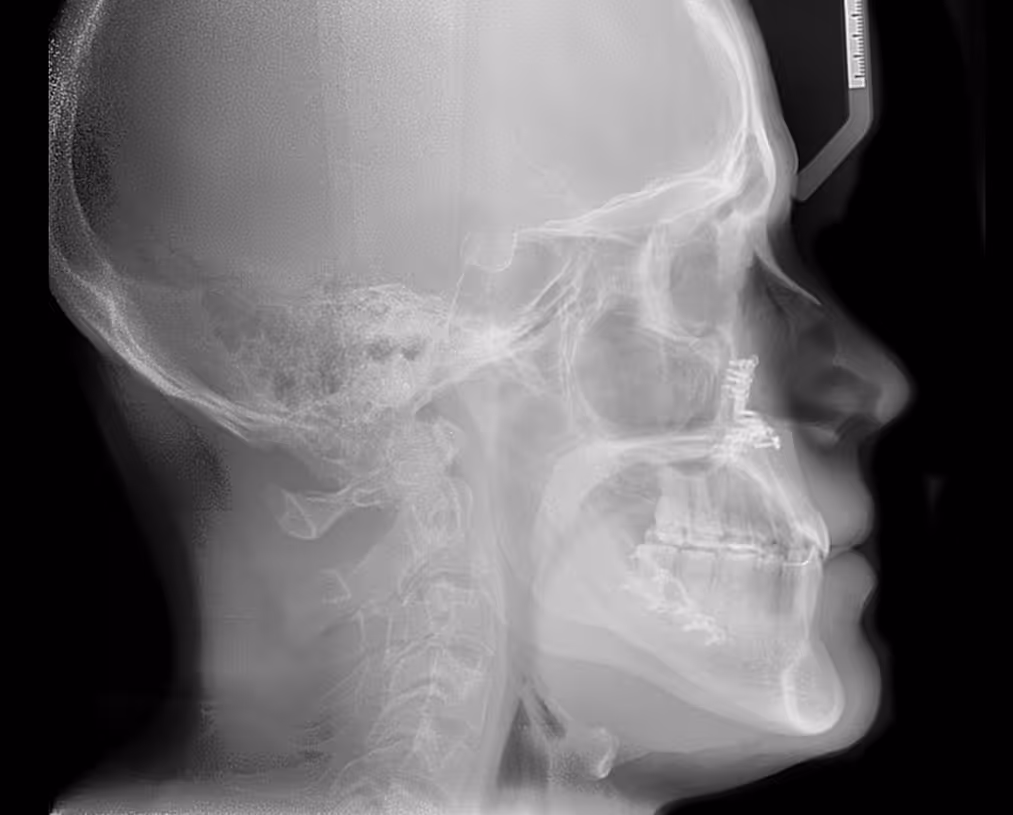

Existen determinados casos en los que la diferencia entre la posición de los maxilares (maxilar superior y mandíbula) es tan grande que un tratamiento de ortodoncia convencional no será suficiente para corregir la mordida.

En estos casos se realizan tratamientos combinados de ortodoncia y cirugía ortognática.